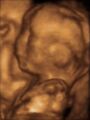

3D ultrasound of 3-inch (76 mm) fetus (about 14 weeks gestational age)

Obstetric ultrasonography is routinely used for dating the gestational age of a pregnancy from the size of the fetus, determine the number of fetuses and placentae, evaluate for an ectopic pregnancy and first trimester bleeding, the most accurate dating being in first trimester before the growth of the foetus has been significantly influenced by other factors.[22] Ultrasound is also used for detecting congenital anomalies (or other foetal anomalies) and determining the biophysical profiles (BPP), which are generally easier to detect in the second trimester when the foetal structures are larger and more developed.[23]

X-rays and computerized tomography (CT) are not used, especially in the first trimester, due to the ionizing radiation, which has teratogenic effects on the foetus.[24] No effects of magnetic resonance imaging (MRI) on the foetus have been demonstrated,[25] but this technique is too expensive for routine observation. Instead, obstetric ultrasonography is the imaging method of choice in the first trimester and throughout the pregnancy, because it emits no radiation, is portable, and allows for realtime imaging.[26]

The safety of frequent ultrasound scanning has not been confirmed. Despite this, increasing numbers of women are choosing to have additional scans for no medical purpose, such as gender scans, 3D and 4D scans.[27] A normal gestation would reveal a gestational sac, yolk sac, and fetal pole.[28]